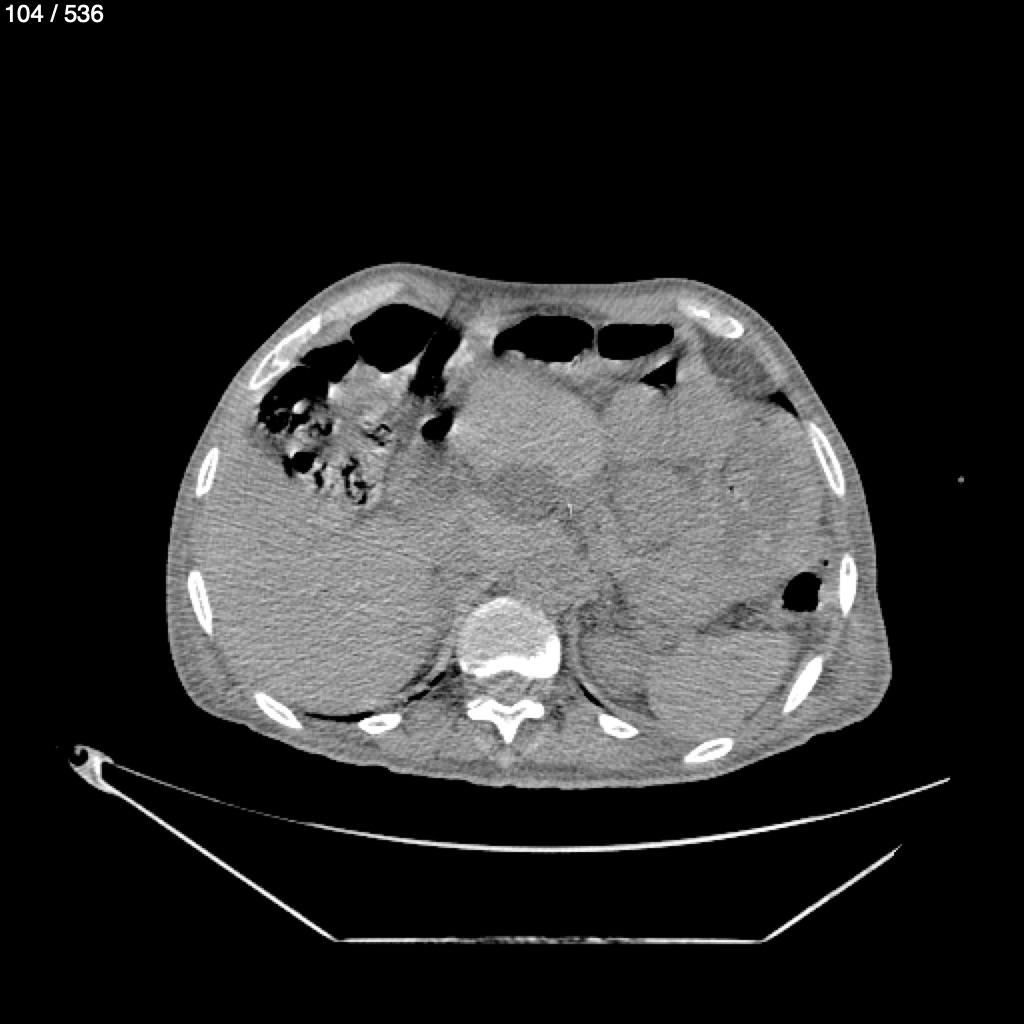

Angel Villalobos Palomeque 73 A - T.C Abdomen Simple